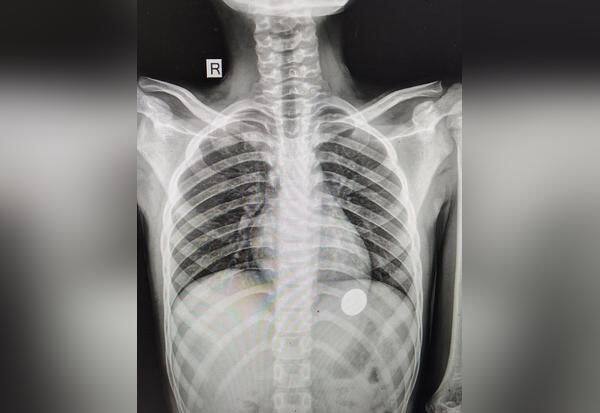

ராமநாதபுரம் : ராமநாதபுரம் அருகே முதுகுளத்துாரைச் சேர்ந்த 12 வயது சிறுவன் 5 ரூபாய் நாணயத்தை தவறுதலாக விழுங்கினார். இந்த நாணயம் தொண்டை வழியாக உணவுக்குழாயில் இறங்கியதால் உயிர் தப்பினார்.

முதுகுளத்துாரை சேர்ந்த கோபி வெளி நாட்டில் பணிபுரிந்து வருகிறார். இவரது மகன் சுதன்மூர்த்தி 12, முதுகுளத்துாரில் உள்ள பள்ளி ஒன்றில் 7 ம் வகுப்பு படிக்கிறார். ஒரிரு நாட்களுக்கு முன் இவர் வீட்டில் 5 ரூபாய் நாணயத்தை வாயில் போட்டு விளையாடிக்கொண்டிருந்தார். அப்போது அவர் நாணயத்தை தவறுதலாக விழுங்கினார். அருகில் இருந்தவர்கள் அவரை உடனடியாக ராமநாதபுரம் அரசு மருத்துவக்கல்லுாரி மருத்துவமனை அவசர சிகிச்சை பிரிவில் அனுமதித்தனர்.

டாக்டர்கள் எக்ஸ்ரே எடுத்து பரிசோதித்தனர். நாணயம் தொண்டை பகுதியில் சிக்கியிருந்தது. பிறகு அந்த நாணயம் உணவுக்குழாய் வழியாக வயிற்றுப்பகுதிக்கு இறங்கியதால் உயிர் தப்பினார். இதையடுத்து டாக்டர்கள் இயற்கை உபாதையை கழிக்கும் போது நாணயம் வெளியே வந்துவிடும் என்பதால் பயப்பட வேண்டியதில்லை என கூறினர். அதன்படி நாணயம் வெளியேறியதையடுத்து சிறுவன் வீட்டிற்கு அனுப்பி வைக்கப்பட்டார்.